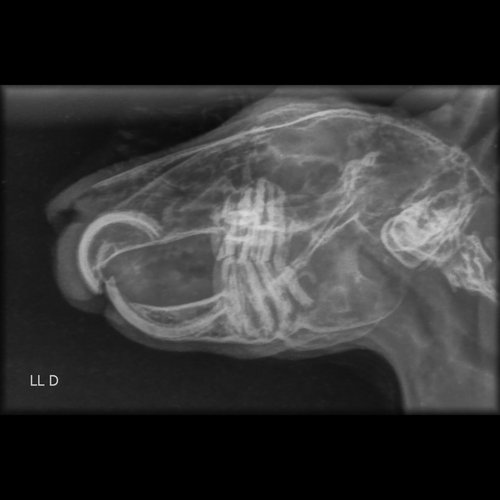

O resultado não foi nada bom… Além de ter um crescimento absurdo dos dentes da frente, os de trás também estão tortos e cresceram d+!!!

Veja o raio-x:

Com isso, ele não consegue comer bem e precisa de cirurgia urgente.